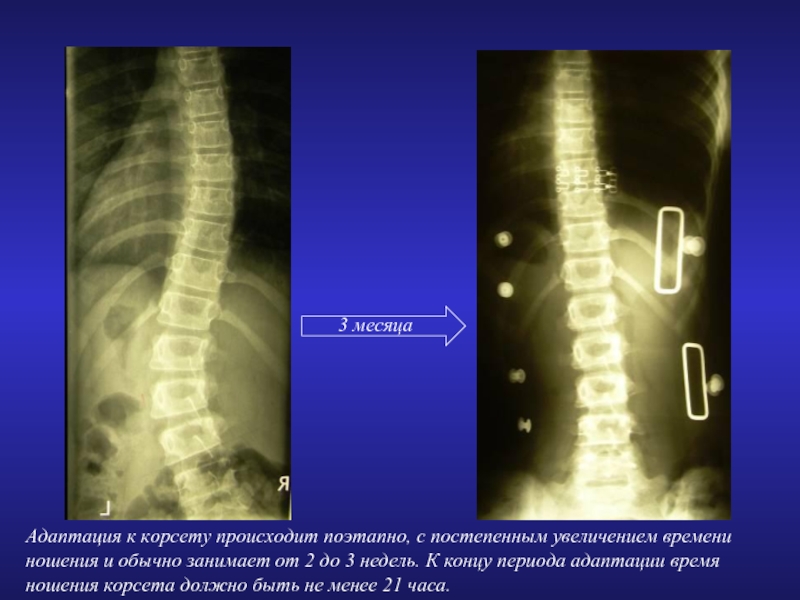

3 месяца

Адаптация к корсету происходит поэтапно, с постепенным увеличением времени ношения

и обычно занимает от 2 до 3 недель. К концу периода адаптации время ношения корсета должно быть не менее 21 часа.